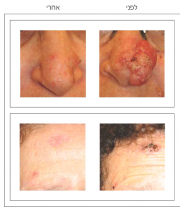

| 17:29, 11 באוגוסט 2014 | BCC-01.png (קובץ) |  |

209 קילו־בייטים | Motyk | 1 | |